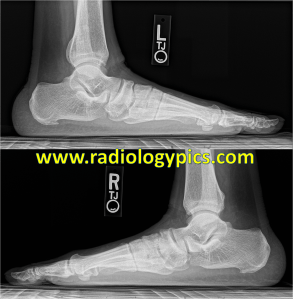

History: 35 year old male with foot pain.

This is the appearance of pes planus, or flatfoot, which occurs in up to 20% of adults with no other abnormalities.

There are many contributors to pes planus deformity, including hindfoot valgus shown by increased talocalcaneal angle to greater than 45 degrees, midfoot sag or lisfranc ligament injury, and forefoot pronation (seen as overlapping metatarsals in the images above). Pes planus can be idiopathic, due to posterior tibialis tendon injury, charcot joint, lisfranc ligament injury, rheumatoid arthritis, or tarsal coalition. It is important to always obtain weightbearing films to assess for alignment, and compare with the contralateral foot.